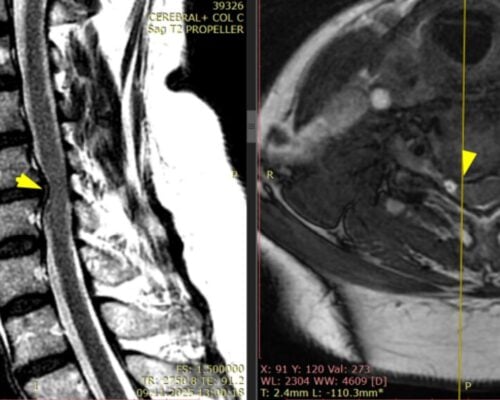

Studiu de caz: Spondiloză cervicală cu compresie medulară tratată prin decompresie ultra-laterală minim-invazivă – Recuperare neurologică rapidă

Spondiloza cervicală reprezintă una dintre cele mai frecvente cauze de afectare progresivă a măduvei spinării la pacienții peste 50 de ani. Problema majoră nu este lipsa tratamentului, ci întârzierea diagnosticului, deoarece simptomele inițiale sunt adesea subtile și atribuite procesului normal de îmbătrânire. Pacienții descriu frecvent dificultăți în activități fine, scăparea obiectelor din mână sau senzația […]